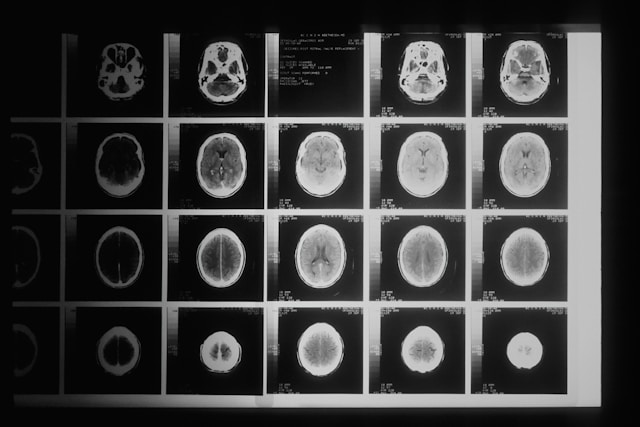

Глиобластома разрушает костную ткань черепа